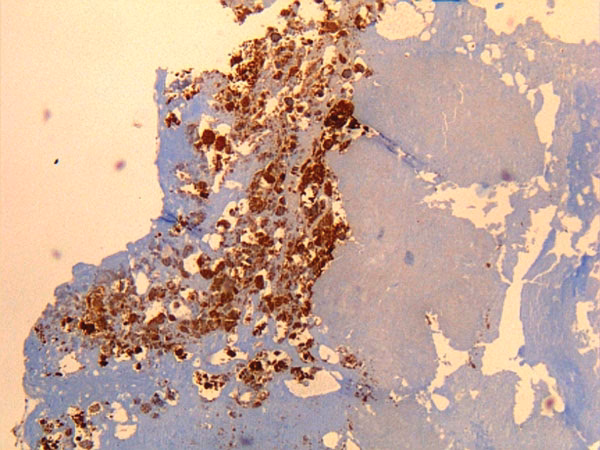

Hos små drøvtyggere er Q-feber primært en reproduktionssygdom. Det mest dramatiske tegn er pludselige og talrige aborter, især i den sidste del af drægtigheden. I en nyligt inficeret besætning kan dette eskalere til det, der kaldes en abortstorm, hvor en stor procentdel af de drægtige dyr aborterer over en kort periode. Andre tegn inkluderer for tidlige fødsler, dødfødsler og fødsel af svage lam eller kid, som har lav overlevelsesrate. Disse hændelser udgør ikke kun et alvorligt velfærdsproblem, men også en massiv kilde til smittespredning, da moderkager og fostre fra disse aborter indeholder ekstremt høje koncentrationer af Coxiella burnetii.